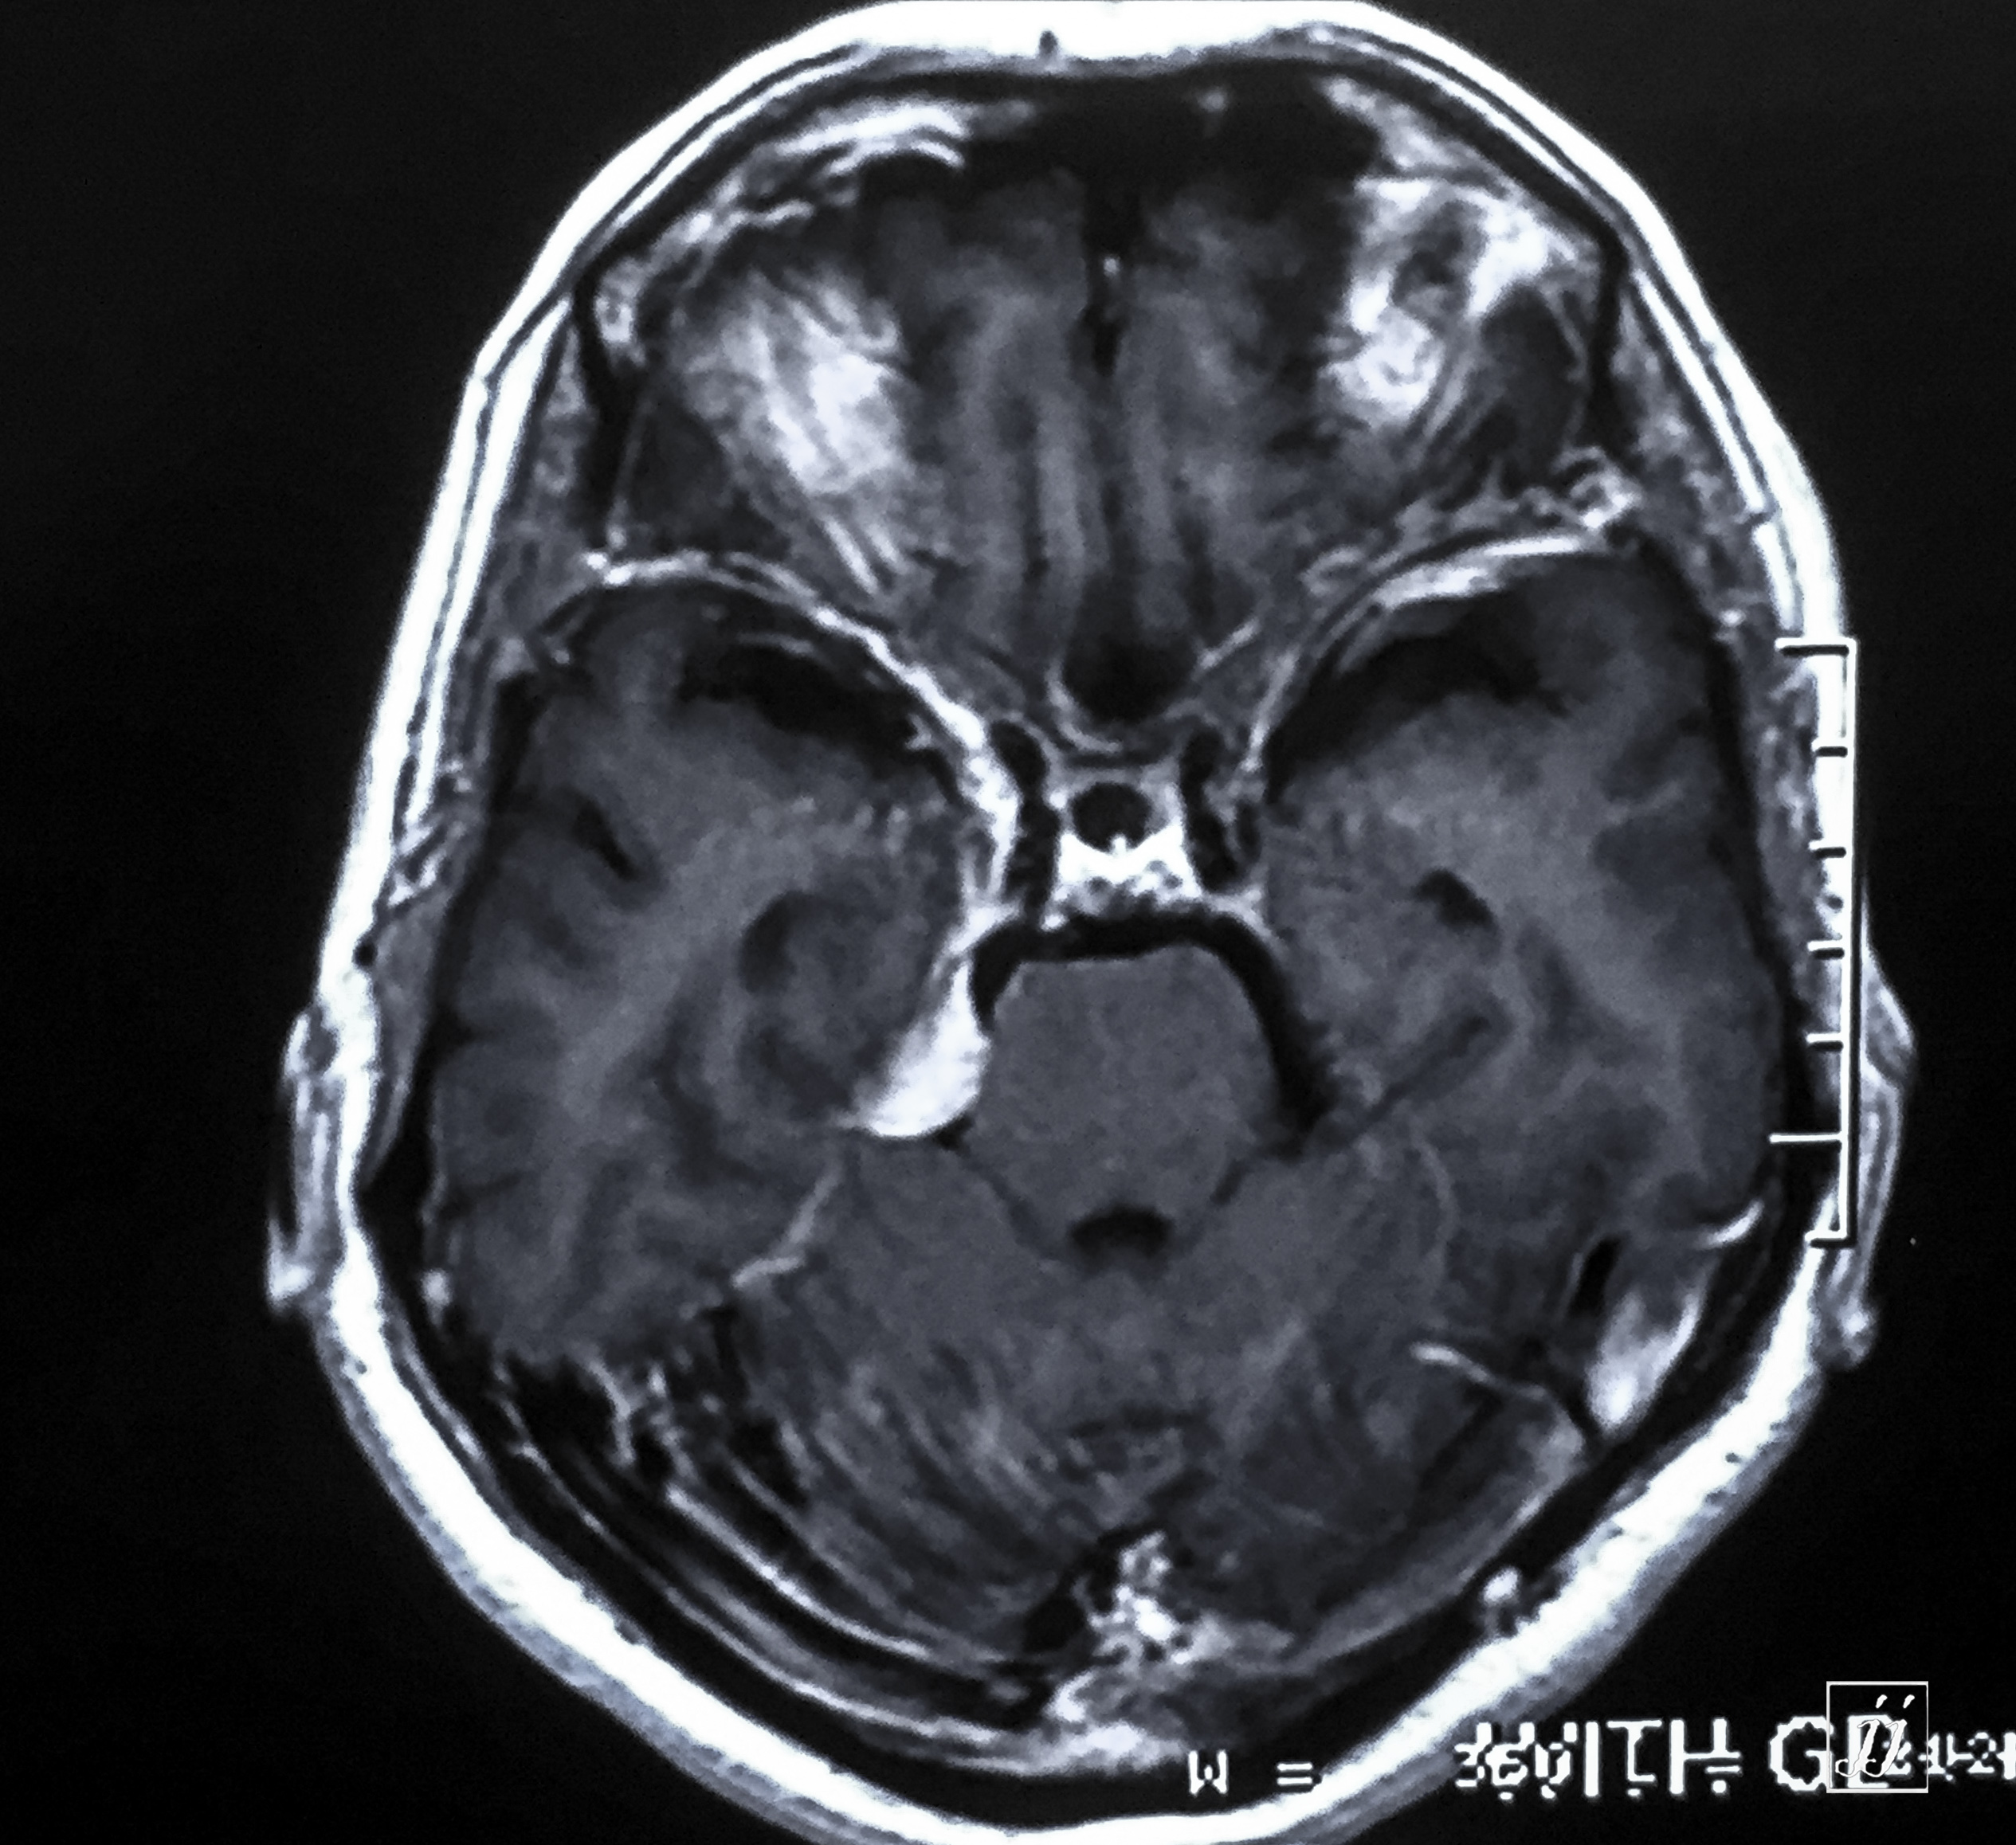

Brain- small right CPA Meningioma (2)